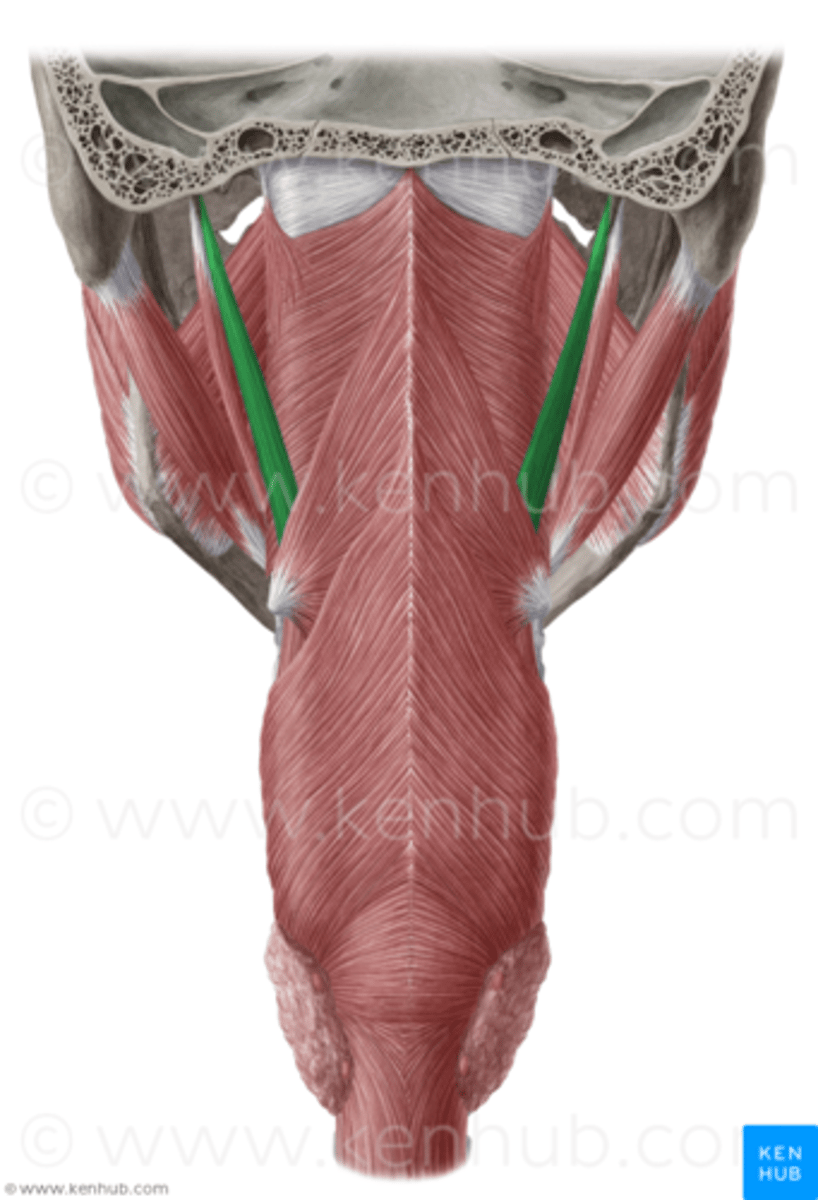

Superior Constrictor Figure

Superior Constrictor Description

Weakest, but most complex of the three

Forms nasopharyngeal and upper

oropharyngeal walls

Origin - sphenoid, mandible, pterygomandibular ligament

Course - posterior, then medial

Insertion - midline raphe

Action - may contribute to velopharyngeal closure by moving posterior wall of pharynx

anteriorly